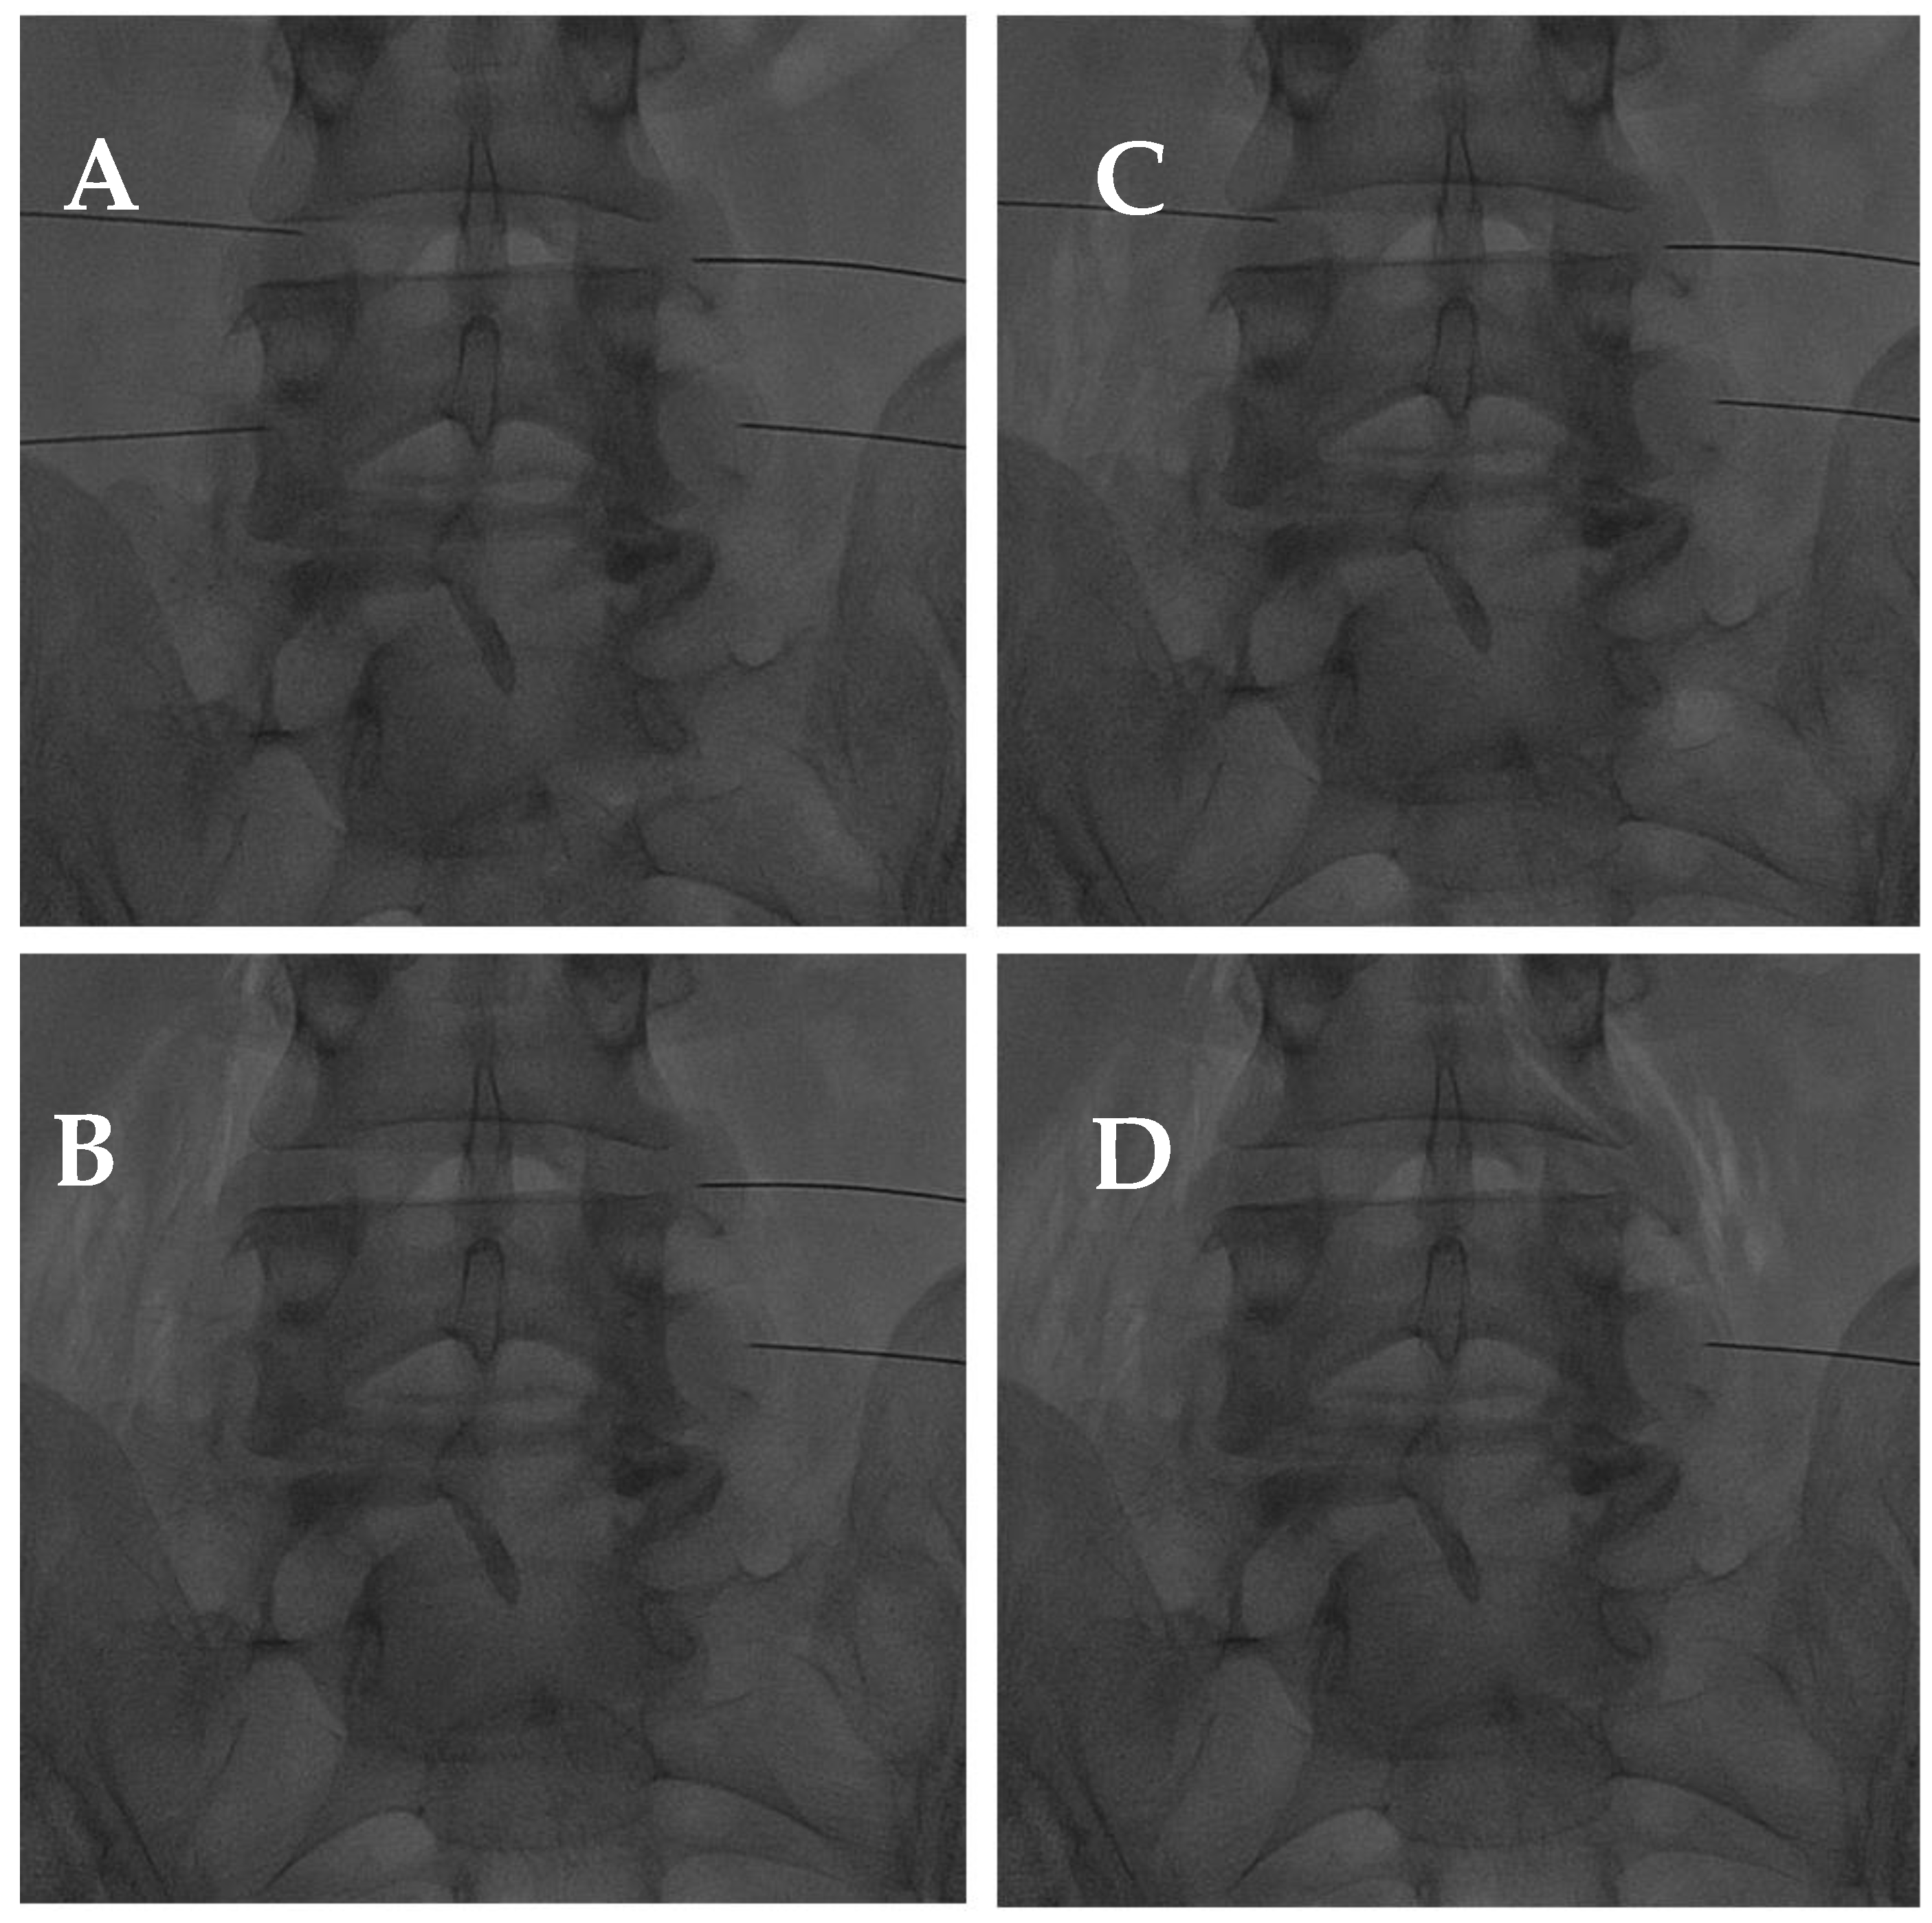

2.2.2. Transforaminal Approach

- Bonetti, M.; Fontana, A.; Cotticelli, B.; Volta, G.D.; Guindani, M.; Leonardi, M. Intraforaminal O(2)-O(3) versus periradicular steroidal infiltrations in lower back pain: Randomized controlled study. Am. J. Neuroradiol. 2005, 26, 996–1000. [Google Scholar]

- Andreula, C.F.; Simonetti, L.; De Santis, F.; Agati, R.; Ricci, R.; Leonardi, M. Minimally invasive oxygen-ozone therapy for lumbar disk herniation. Am. J. Neuroradiol. 2003, 24, 996–1000. [Google Scholar] [PubMed]

- Zhang, Y.; Ma, Y.; Jiang, J.; Ding, T.; Wang, J. Treatment of the lumbar disc herniation with intradiscal and intraforaminal injection of oxygen-ozone. J. Back. Musculoskelet. Rehabil. 2013, 26, 317–322. [Google Scholar] [CrossRef]

- Muto, M.; Andreula, C.; Leonardi, M. Treatment of herniated lumbar disc by intradiscal and intraforaminal oxygen-ozone (O2-O3) injection. J. Neuroradiol. 2004, 31, 183–189. [Google Scholar] [CrossRef] [PubMed]